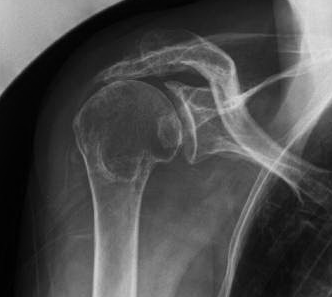

Elle survient le plus souvent chez des sujets âgés et s'accompagne d'une ascension de la tête humérale sous l'acromion à l'origine d'une impossibilité à monter le bras. Si la rupture de la coiffe n'est pas réparable, on peut envisager alors la mise en place d'une prothèse totale inversée d'épaule.

Exemple d'arthrose excentrée de l'épaule à cause d'une ascension de l'humérus